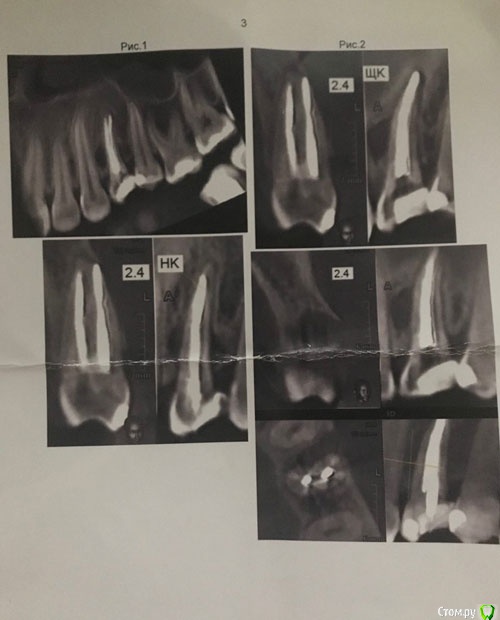

Ситуация такая: пару лет назад на десне появился свищ (24 зуб), мой лечащий врач сделала снимок (ничего не увидела), проколола свищ, приложила какую-то примочку с лекарством и рекомендовала полоскать и смотреть динамику. Года полтора я проходила то с появляющимся, то со вновь исчезающим свищом. После посещения другого врача выяснилось, что внутри установлен штифт, и все-таки есть какие-то проблемы в корне, но по снимку было непонятно - то-ли кариес корня, то-ли механическое повреждение. Но исходя из локализации воспаления, было показано удаление зуба с последующим протезированием. На тот момент я кормила грудью, с удалением решила повременить. И через пол-года случилось воспаление десны с острой болью на фоне сниженного иммунитета из-за простуды. В срочном порядке обратилась к третьему специалисту, - мой зуб был распломбирован, установлена временная пломба. Врач дал направление на кт.

Цитирую описание: "зуб депульпирован. Коронковая часть восстановлена пломбой. Щечный канал зуба запломбирован до апекса. В небный канал установлен штифт до 1/2 длины корня, далее канал зуба запломбирован, не доходя до апекса на 2.0мм, материал доведен до мезиальной поверхности апикальной трети корня. Периодонтальное пространство в области апекса корня зуба не расширено. В области средней трети корня зуба с мезиальной стороны определяется дестркуция костной ткани овоидной формы, однородной структуры, размерами до 3.1х5.4х7.4мм (ШхВхГ), с ровными четкими контурами. Определяется дефект щечной кортикальной пластинки челюсти в области очага. Заключение: Хронический периодонтит. Периодонтно-парадонтальное поражение зуба. Объемное образование левого верхнечелюстного синуса, дифференцровать с ретенционной кистой."

Врач сказал, что зуб безнадежен, признаки перелома корня на лицо.